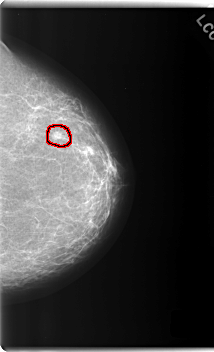

C_0187_1.LEFT_CC

LEFT_CC LINES 5984 PIXELS_PER_LINE 3632 BITS_PER_PIXEL 12 RESOLUTION 50 OVERLAY

FILE: C_0187_1.LEFT_CC.OVERLAY

TOTAL_ABNORMALITIES 1

ABNORMALITY 1

LESION_TYPE MASS SHAPE ROUND MARGINS SPICULATED

ASSESSMENT 5

SUBTLETY 5

PATHOLOGY MALIGNANT

TOTAL_OUTLINES 1

BOUNDARY